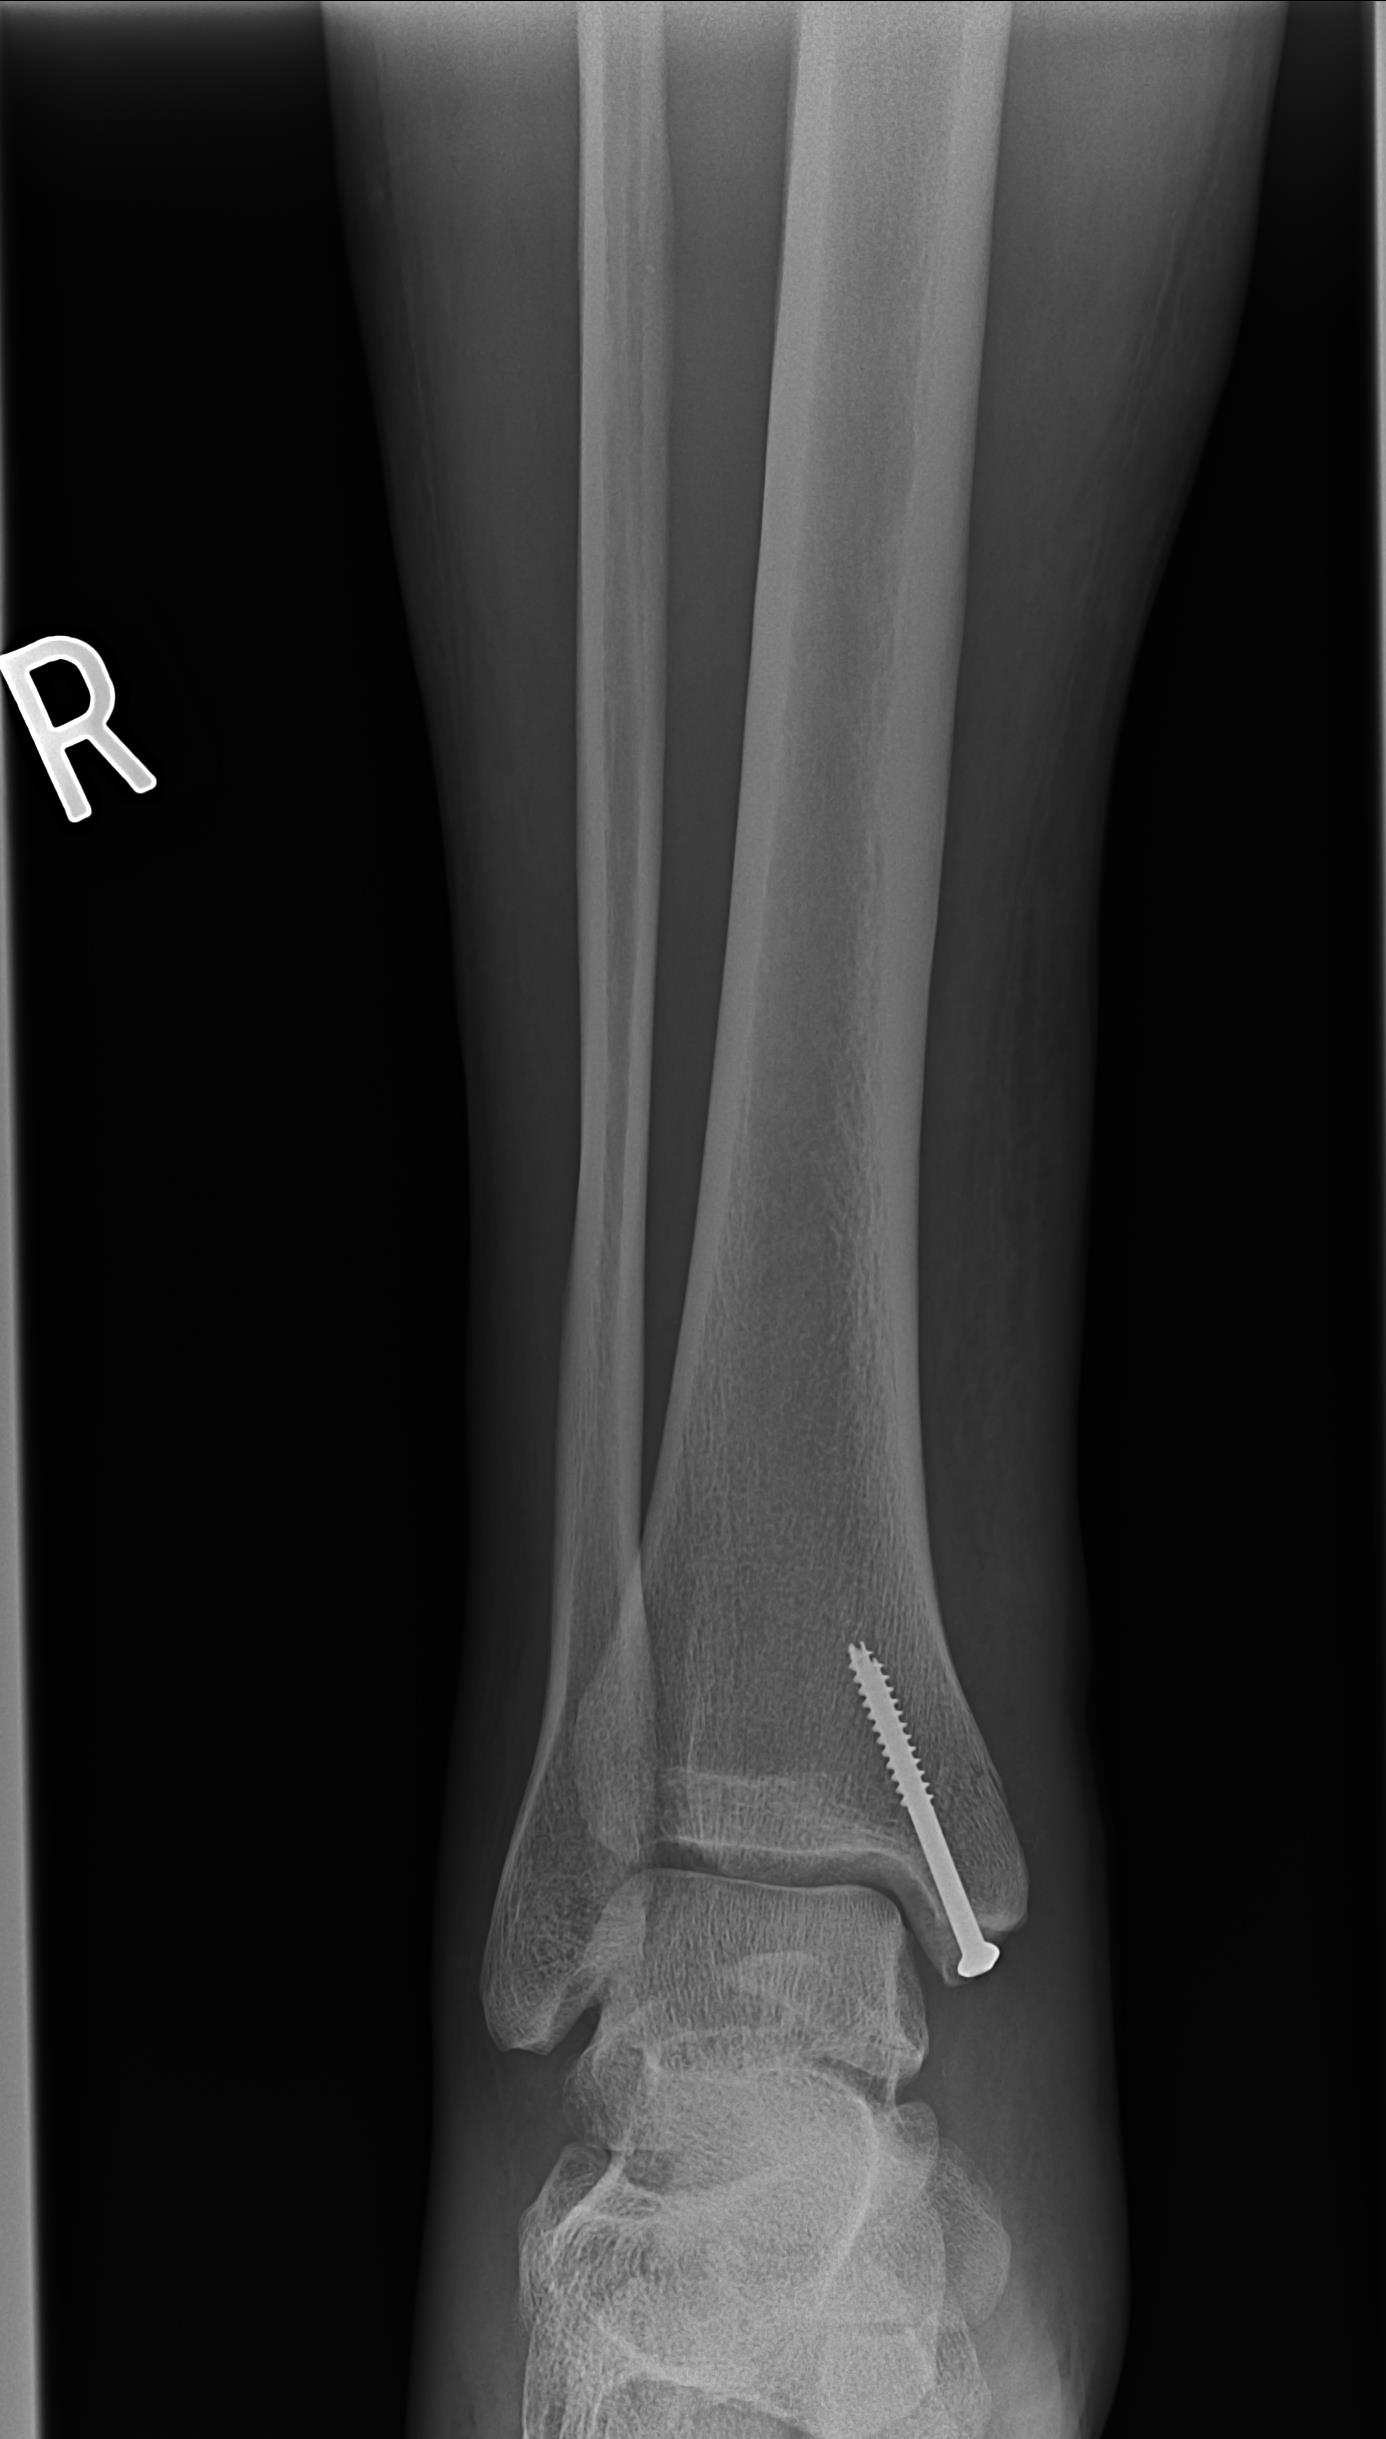

FixedAnkle1